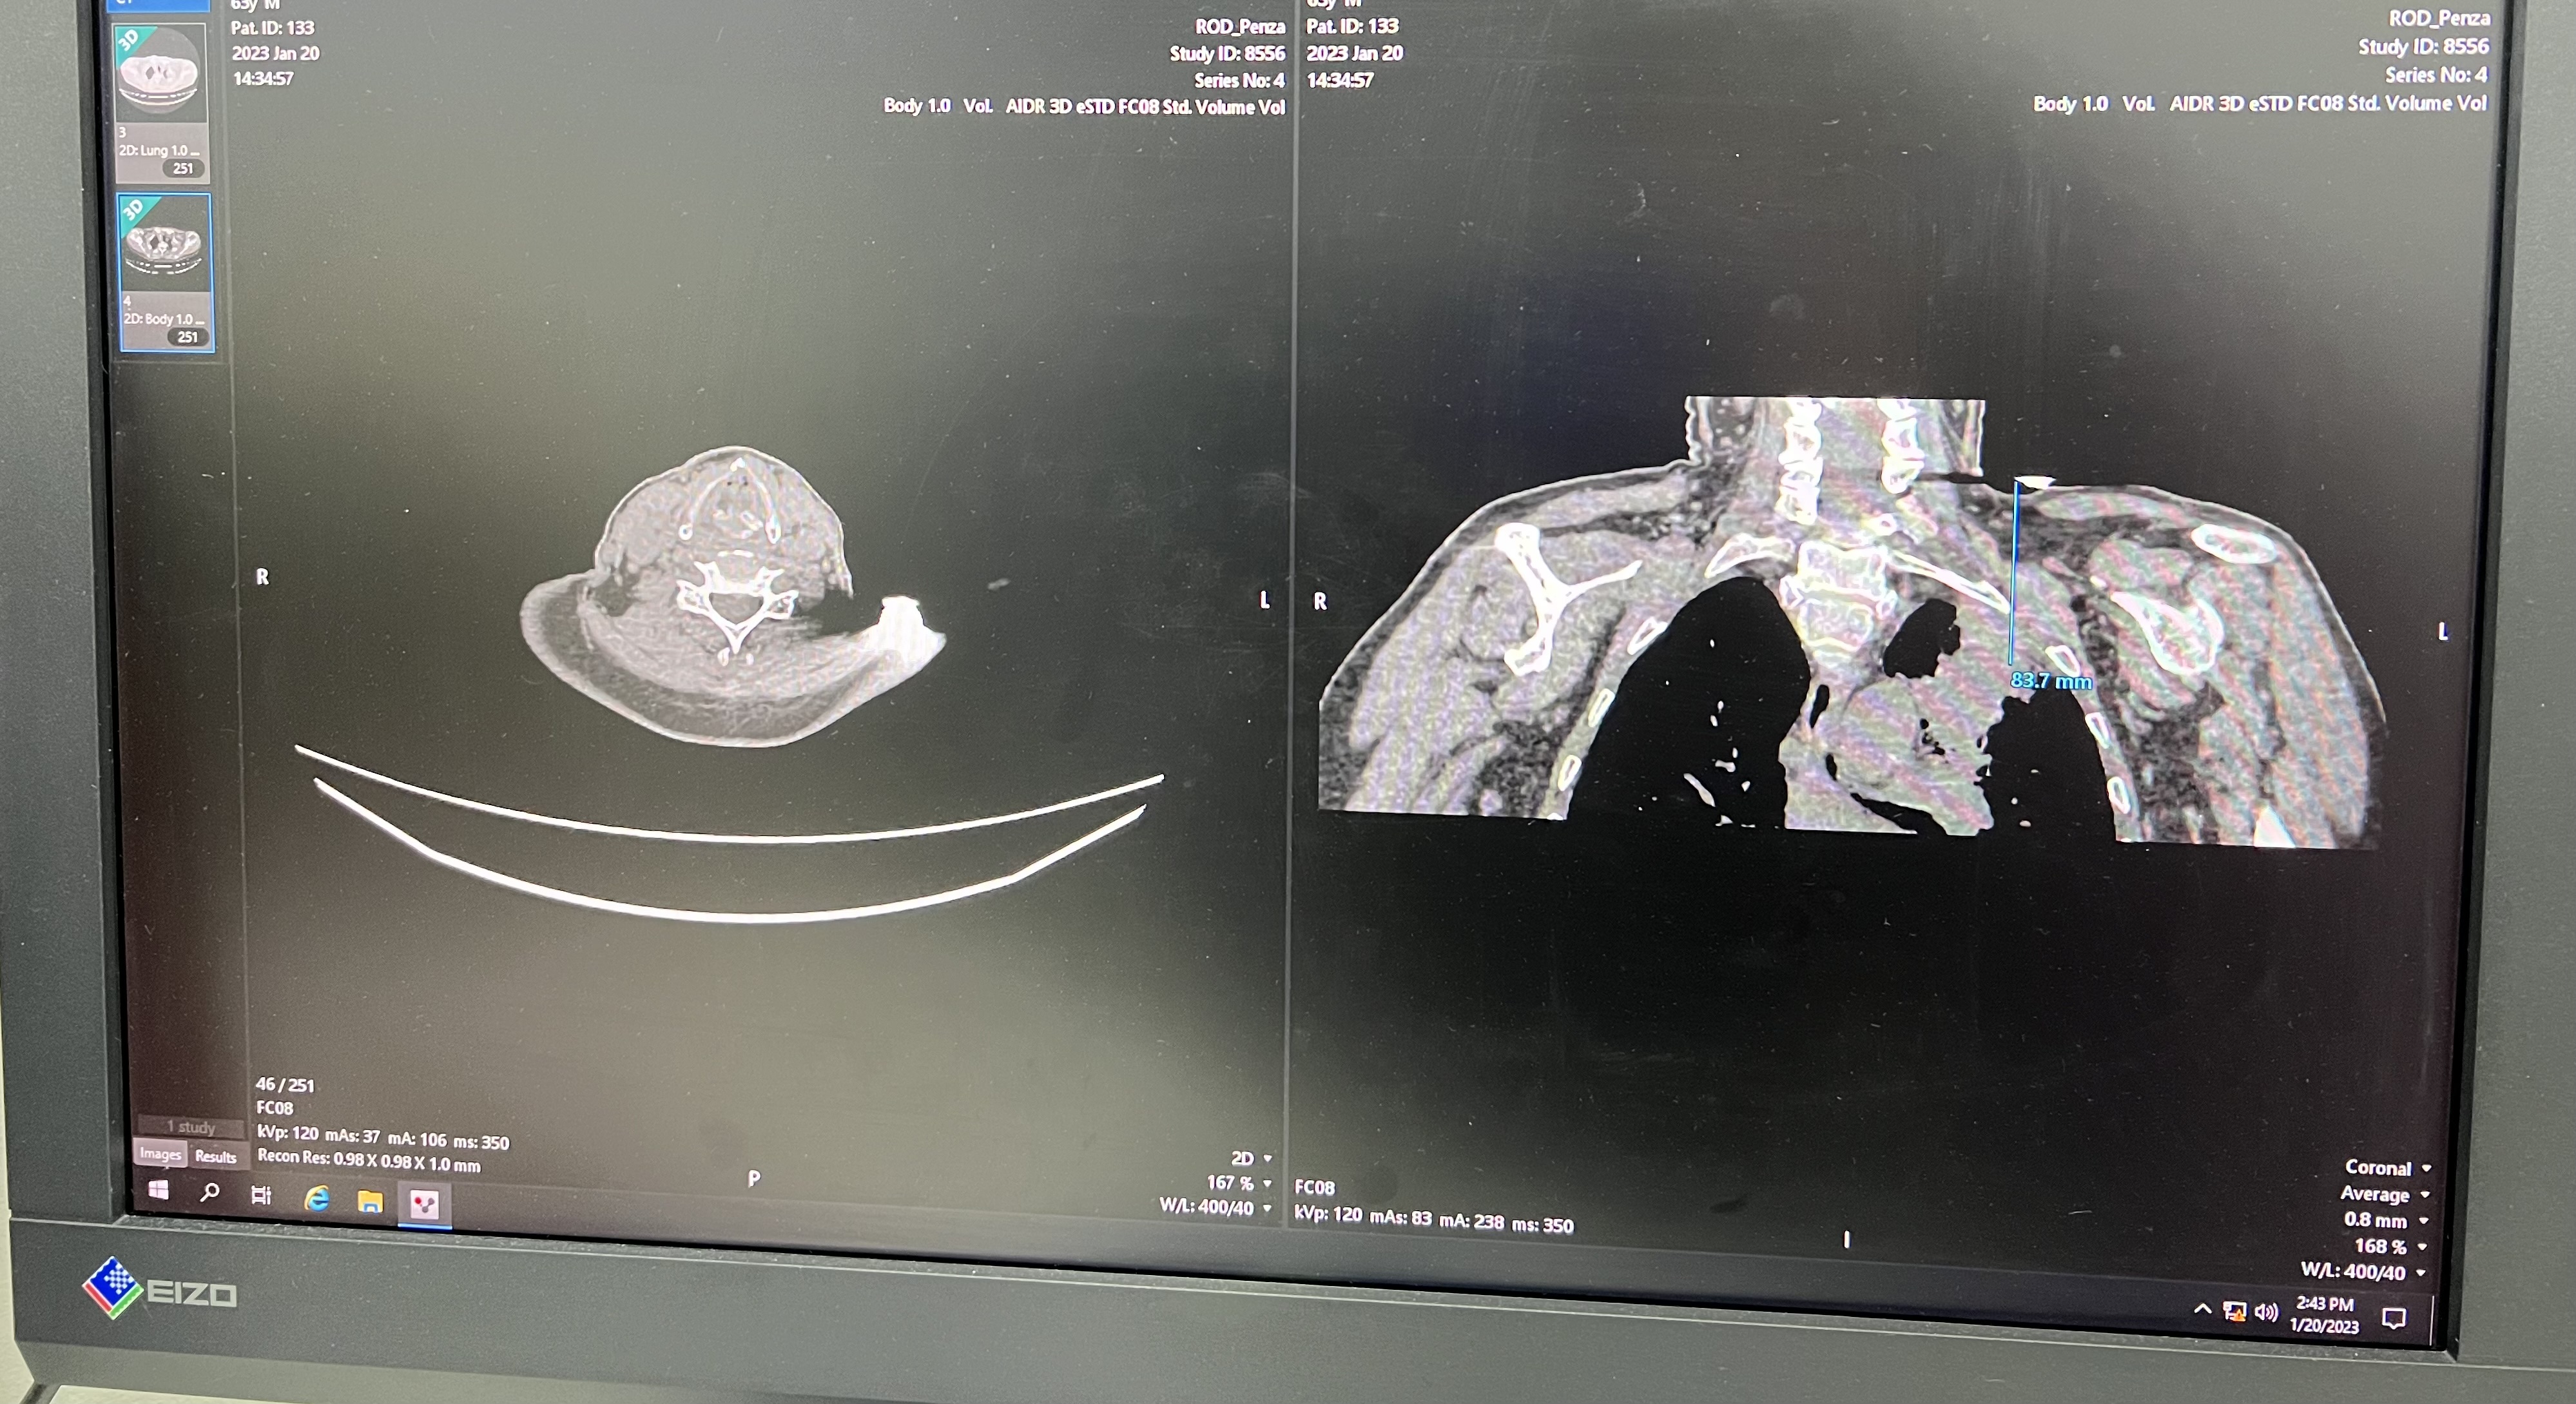

Врачи областного онкологического диспансера используют КТ-ассистированную трансторакальную биопсию новообразований легких - методику, которая позволяет поставить точный диагноз при сложных раковых заболеваниях. Это малоинвазивная диагностическая процедура получения гистологического материала с помощью специальной иглы под контролем компьютерной томографии. Цель данной процедуры - получение образцов материала из внутренних органов при подозрении на наличие злокачественных новообразований с целью уточнения диагноза.

«При опухоли лёгких иногда требуется получить морфологическую верификацию опухоли. Иногда это делается при операции, а иногда путём трансторакальной пункции, то есть через грудную стенку. Большие опухоли можно рассмотреть на снимках, из более сложных мы получаем материал для гистологической экспертизы через рентген-навигацию. Но есть случаи, когда опухоли очень неудобно расположены, например, близко к сосудам. В таких случаях, мы и используем метод КТ-ассистированной трансторакальной биопсии новообразований, чтобы установить точный диагноз и назначить правильное лечение. Такая процедура используется нечасто, в самых сложных случаях», - рассказал торакальный хирург онкологического диспансера Александр Горшенёв.

«Сначала мы проводим прицельное сканирование и устанавливаем метку, по которой будем ориентироваться в дальнейшем, чтобы поставить троакар или иглу. Затем мы считаем глубину прокола, координаты, отправные точки и делаем сканирование на предмет выявления пневмоторакса, если мы пунктировали (прокалывали) грудную клетку. Таким образом, можно пропунктировать периферические образования лёгких, позвоночника, рёбер, мягких тканей», - говорит Юлия Васильева.

Преимущество такого метода биопсии заключается в том, что в процессе получения гистологического материала, медики видят, где стоит пункционная игла или троакар. Изображение можно получить в любой плоскости или в 3D-формате. Внедрение КТ-ассистированной трансторакальной биопсии новообразований позволяет ставить точный диагноз и подбирать эффективные методы лечения пациентов.